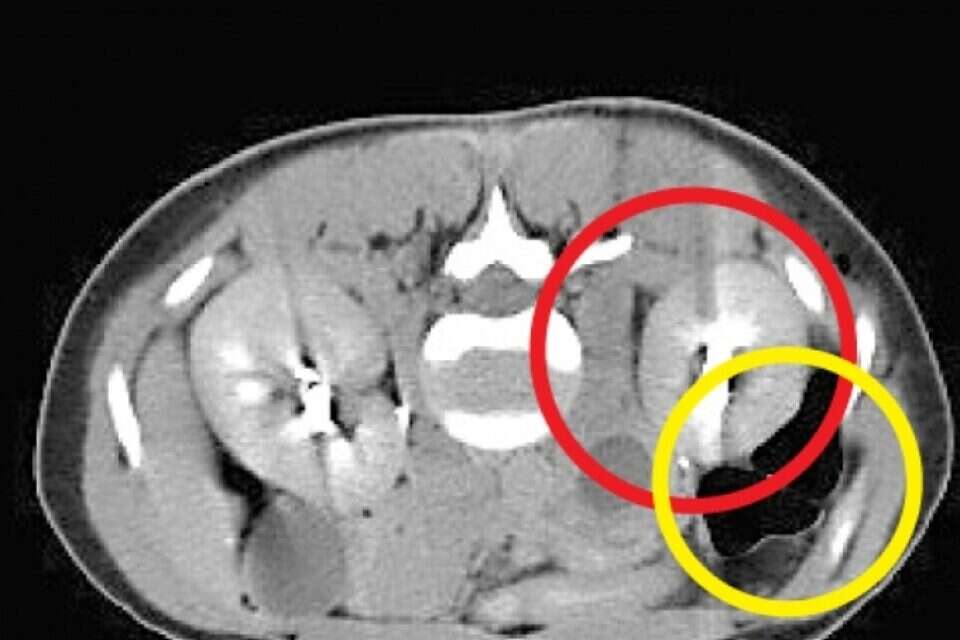

הרופא לא האמין למראה בדיקת האולטרסאונד: תוצאות בדיקות המעבדה הראו שבתום טיפולי הפריה של מטופלת הושג הריון, אך בבדיקת ההדמיה לא נראה עובר בחלל הרחם. הסיפור המיוחד התרחש בבית החולים הדסה, שם טיפלו באזרחית קפריסאית (30) שנשאה הריון נדיר במיוחד. העובר לא היה ברחם שלה וגם לא בחצוצרות, מקום שבו בדרך כלל משתרשים הריונות מחוץ לרחם. בבדיקת האולטרסאונד נמצא שההריון השתרש בין הכליה לבין כלי דם גדול שמוביל אליה. מדובר בדיווח השני בעולם על מקרה שכזה. "הרופא שליווה את ההריון בקפריסין יצר איתנו קשר והמלצנו לו להטיס את האישה אלינו", אמר פרופ' נרי לאופר, מנהל המערך למיילדות ולגינקולוגיה בבית החולים הדסה, "הריון כזה עלול לסכן את חייה של האישה באופן מיידי. השליה של העובר חודרת לתוך כלי הדם הגדול ועלול היה להיווצר מצב שאבי העורקים של אותה אישה היה מתפוצץ בחלל הבטן וגורם למותה". בהדסה התגייסו להטיס את האישה לארץ באמצעות "אמבולנס מעופף" - מסוק עם ציוד רפואי וליווי רפואי שנמצא בבית החולים הירושלמי. לדברי פרופ' לאופר, אי אפשר היה להמשיך את ההריון הזה בשל הסיכון הרב לחיי האישה ולכן הוחלט לבצע הפסקת הריון: "לאחר ביצוע הפסקת ההריון ראינו דם בכמות גדולה שהצטבר מתחת לכליה. קראנו לכירורגים מומחים לכלי דם משום שהיה חשש שהאישה תאבד את הכליה. למרות הזרקת חומר שחוסם את כלי הדם האישה המשיכה לדמם והוכנסה לחדר ניתוח. קיבצנו כמות גדולה של רופאים מומחים, רנטגנולוגים, כירורגים כלליים וכירורגים של כלי דם ובמהלך הפעולה - שנמשכה 48 שעות ברצף - התברר לנו שההריון כבר חדר לכלי דם גדולים". בסופו של דבר הצליחו המנתחים לסגור את כלי הדם מעל ומתחת למקום שבו השתרשה השליה והתפתח ההריון, ולהציל את חייה של האישה בלי לפגוע בכליה שלה. במהלך הניתוח התבררה עובדה מעניינת נוספת - העובר ניקב את ציפוי הבטן ולמעשה חדר לאחוריו. לדברי פרופ' לאופר, "זהו מקרה מאוד נדיר. השכיחות של הריון מחוץ לרחם נעה בין חצי אחוז לאחוז בודד, אך בהריונות שהושגו בהפריה חוץ גופית היא גבוהה יותר ועומדת על 5-2 אחוזים. רוב ההריונות שמחוץ לרחם נמצאים בחצוצרה ונדיר ביותר שהריון יימצא בחלל הבטן. לצערי, לא היה אפשרי במקרה הזה להציל את ההריון, אך אני שמח שאפשר היה להציל את האישה".

הריון נדיר: העובר התמקם מתחת לכליה

מקרה שני מסוגו בעולם טופל בהדסה • אזרחית קפריסין שנשאה עובר מחוץ לרחם הוטסה לארץ • הרופאים נאלצו להפסיק את ההריון כדי להציל את חיי האישה